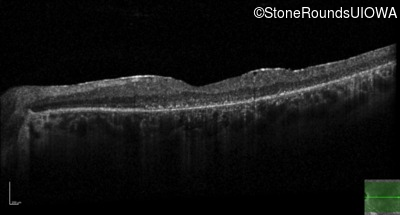

Optical Coherence Tomography - Left - 10/200

Exemplar / OCT Stack

OCT Stack